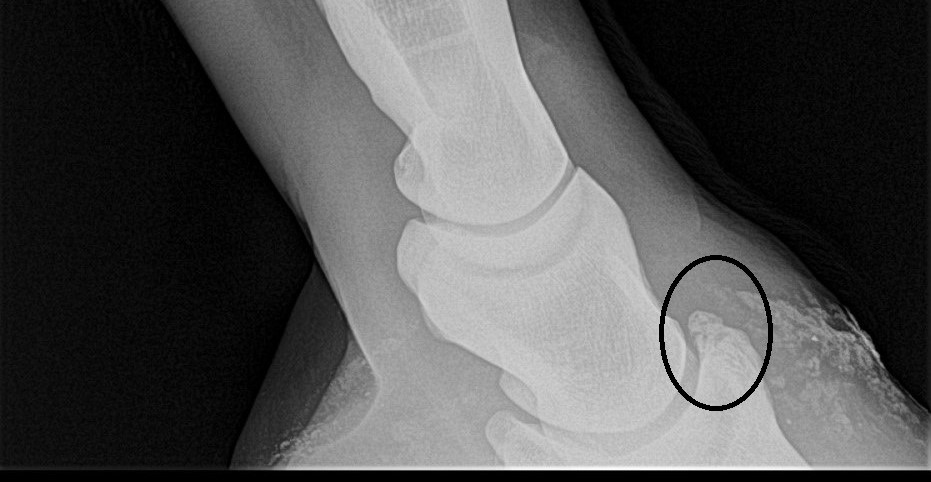

Radiography (X-ray imaging) is one of the most valuable and widely used diagnostic tools in equine orthopedics. Through a fast, non-invasive technique, radiographs allow us to visualize the internal structures of the horse—bones, joints, and specific anatomical details—making it possible to detect orthopedic problems early and improve treatment outcomes in sport horses.

As an equine orthopedic veterinarian (PhD) based in Belgium, I use high-frequency digital radiography to obtain immediate, high-resolution images essential for accurate diagnosis, lameness evaluation, performance monitoring, and pre-purchase examinations across Europe.

Early identification of these problems is crucial to prevent long-term damage and maintain the performance, longevity, and safety of sport horses.